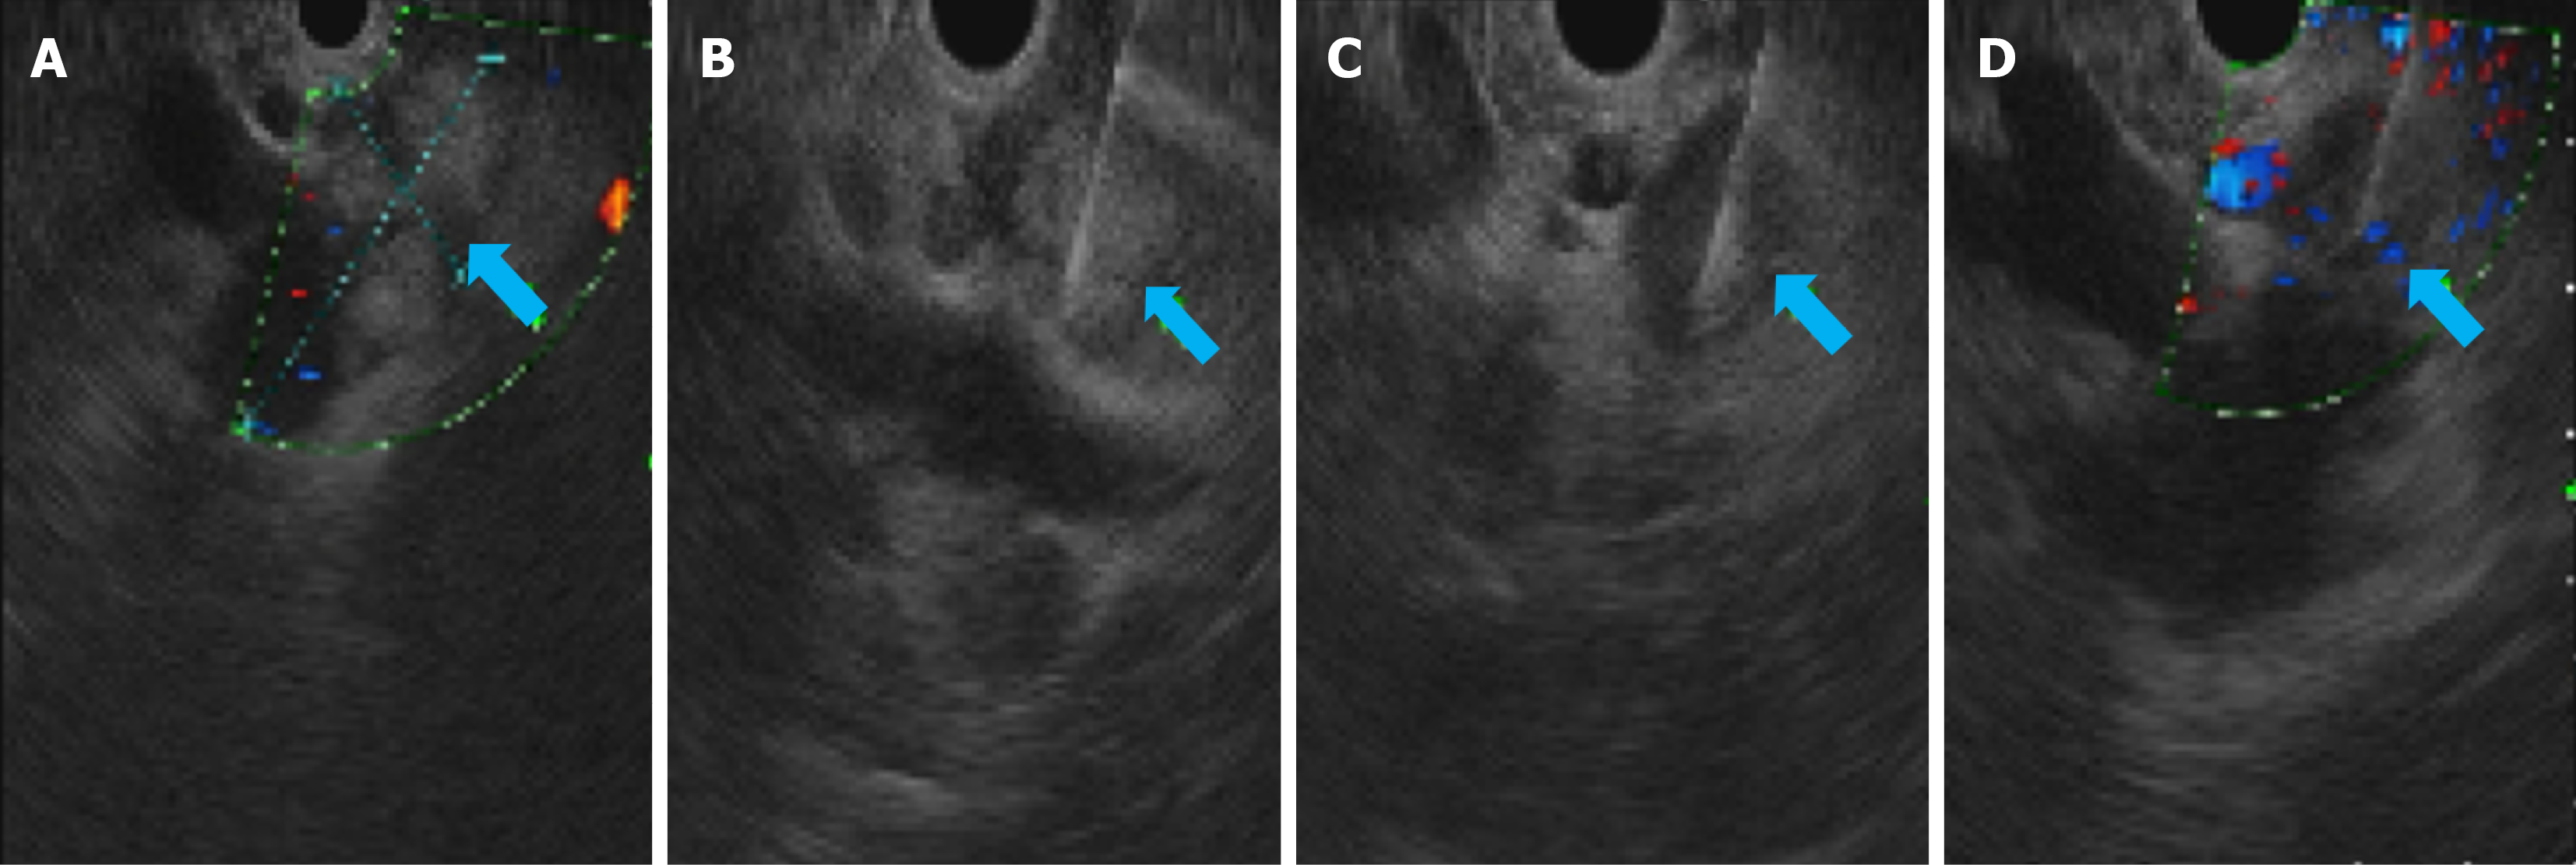

Figure 2 Endoscopic ultrasound-guided fine-needle aspiration biopsy procedure.

A: Ultrasound image of the liver (S1 segment) showing a lesion characterized by low-level echoes, measuring approximately 50.5 mm × 25.5 mm (arrow). Internal changes, including high-intensity echoes, were observed within the lesion. It was observed that the lesion surrounded the portal vein and its confluence and was in proximity to the lower segment of the hepatic portal vein. The surrounding low-intensity lymph nodes appear dispersed; B and C: Ultrasound-guided puncture at the lesion site (arrow); D: Perifocal lymph node puncture (arrow).